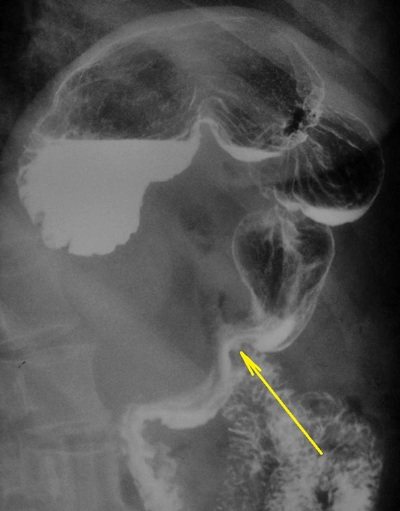

Во время рентгеновского исследования можно увидеть, как орган преобразовывается из роговидной формы в крючковидную после наполнения его контрастным веществом.

По снимку каскадный желудок выглядит следующим образом. Орган имеет перегиб вокруг своей оси. На фоне этого образуется 2 колена: нижнее в виде трубки и верхнее в виде чаши. На передней проекции видно, что свод располагается ниже, чем положено, то есть на уровне привратника.

Во время проведения рентгенограммы контрастное вещество попадает под газовый пузырь. Таким образом можно с высокой точностью исследовать нижнюю часть органа. Чтобы получить верный результат, нужно строго придерживаться всей техники.

Во время исследования врач делает несколько снимков. Обязательно сопоставляются рентгенологические признаки рака желудка. При выявлении выпуклостей доктор заостряет внимание и рассматривает эту зону более тщательно. Газовый пузырь желудка на рентгене не будет заполнен жидкостью. При этом контрастное вещество распространиться по всей верхней части органа.

Основной способ диагностики – рентген с использованием контрастного вещества. В качестве контраста используется суспензия сульфата бария. Специальной подготовки к обследованию не требуется, необходимо только проходить его натощак, после 6–10 часов голодания. Перед процедурой нужно будет выпить 200 мл раствора белого цвета с металлическим привкусом.

При подозрении на наличие патологии врач рентгенолог с целью понять, что это такое – функциональный загиб желудка или органическое нарушение может попросить больного 10 раз с усилием нагнуться. При временном нарушении петли кишечника, сдавливающие орган смещаются и каскады не визуализируются на рентгенограмме. При органических нарушениях после наклонов рентгенологическая картина остается неизменной.